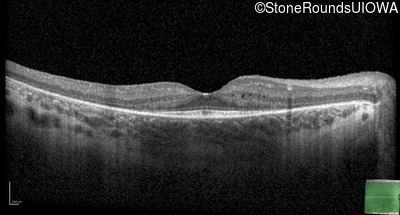

Age at visit: 8 years

OD OS

This 8 year old girl first had trouble trick-or-treating at age 4.

Age at visit: 9 years